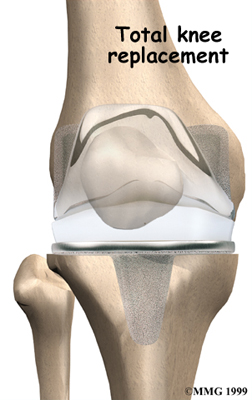

Artificial Knee Replacement

An artificial knee replacement is the ultimate solution for advanced knee OA.

Surgeons prefer not to put a new knee joint in patients younger than 60. This is because younger patients are generally more active and might put too much stress on the joint, causing it to loosen or even crack. A revision surgery to replace a damaged prosthesis is harder to do, has more possible complications, and is usually less successful than a first-time joint replacement surgery.

Related Document: FYZICAL East Kettering's Guide to Artificial Joint Replacement of the Knee